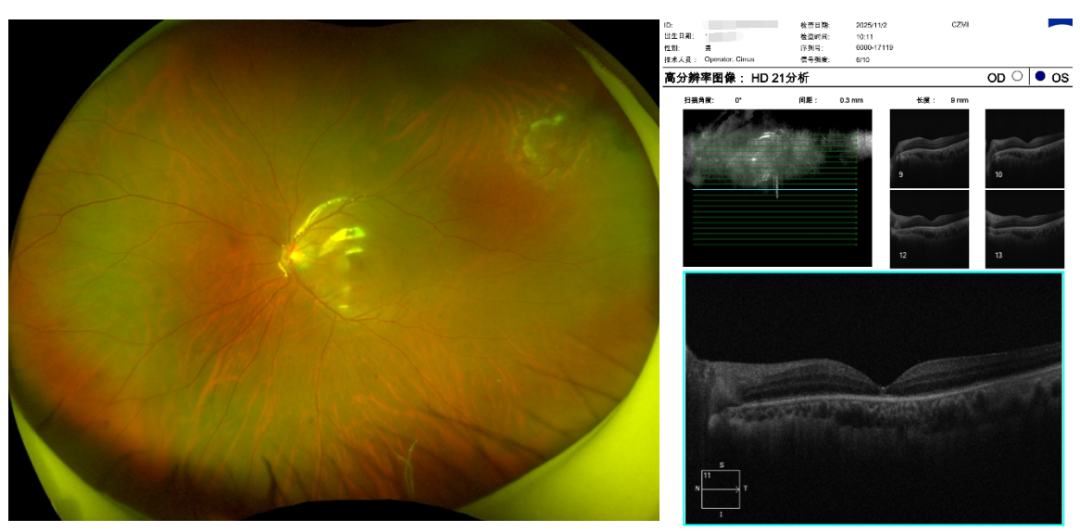

结果令人心惊:右眼周边视网膜也存在多个变性区和裂孔!这意味着,他的右眼同样危机四伏,如同布满了「定时炸弹」,随时可能发展为新的视网膜脱离。

对右眼:立即行预防性视网膜激光光凝术。利用激光在裂孔周围精准「焊接」,构筑一道坚实的「堤坝」,将视网膜脱离的风险扼杀在摇篮之中。

检查证实,他的 视网膜已完全平伏复位,激光斑清晰可见。脱离的「底片」被成功抢救回来。